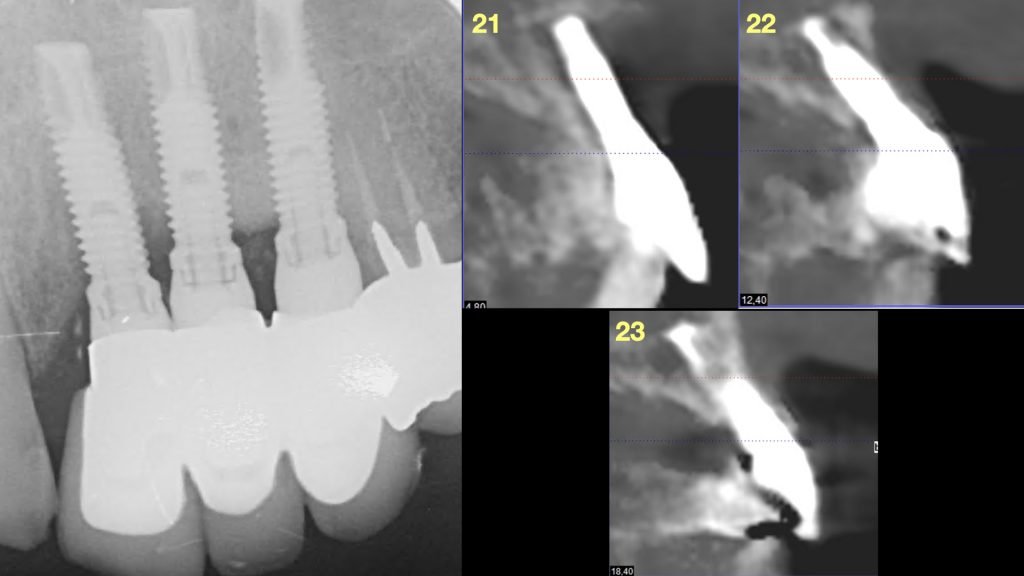

A la exploración radiográfica se observa la pérdida ósea interproximal de los 3 implantes confirmándose así el diagnóstico de periimplantitis (Figura 2).

Radiografía 3D donde se puede apreciar la atrofia ósea.